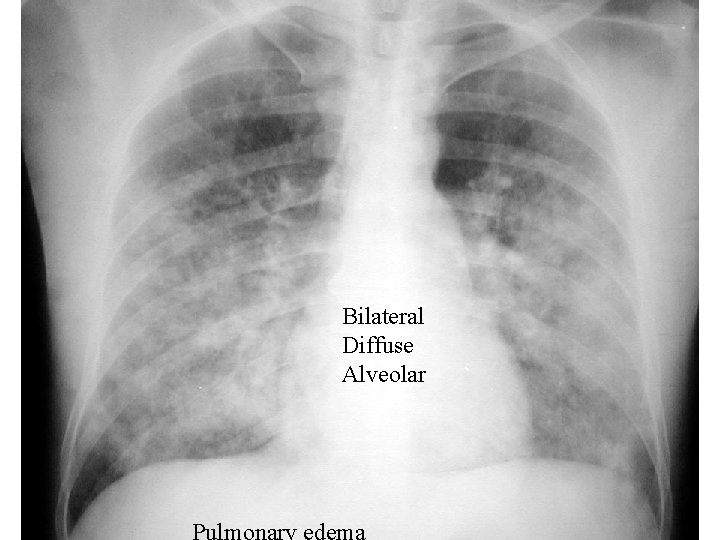

Pulmonary edema

Bilateral Diffuse Alveolar